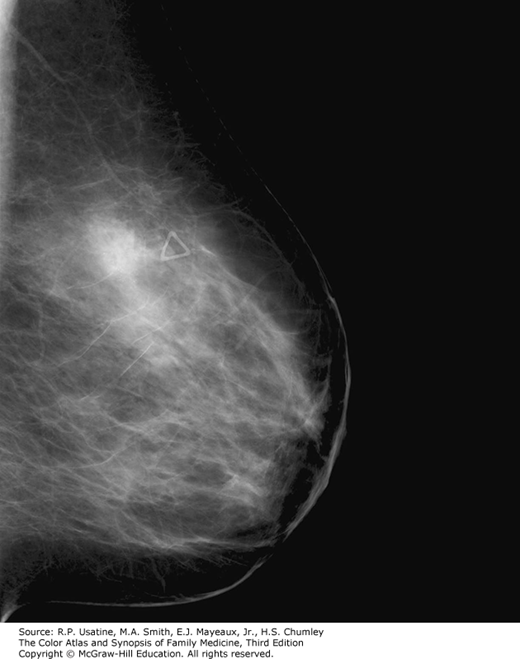

A mammogram that demonstrates an irregular mass with possible local spread. (Reproduced with permission from John Braud, MD.)